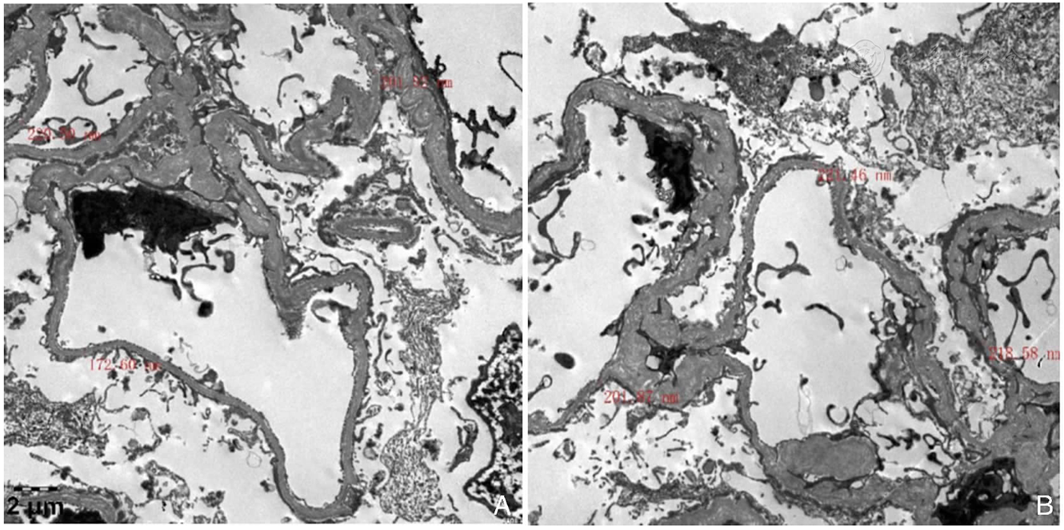

图4 肾组织电镜表现注:A:电镜×6 000;B:电镜×6 000;肾小球基底膜偏薄;未见确切电子致密物沉积